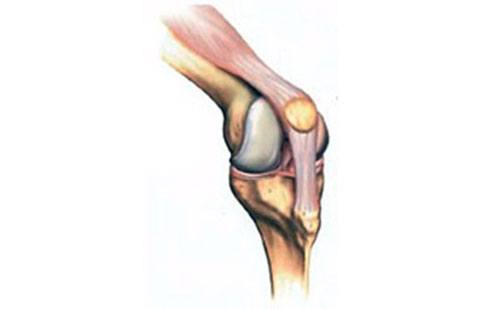

O joelho é uma articulação composta por três ossos: o osso da coxa (denominado fêmur), o osso da tíbia (perna) e a patela (osso da frente). Quando você dobra ou estica o seu joelho, o osso da coxa e o osso da perna deslizam de forma suave. A cartilagem articular cobre e protege os ossos ao redor do joelho. Entre os ossos existem os meniscos que agem absorvendo impacto.A patela encontra-se presa na musculatura da frente do joelho e auxilia nesse movimento. A presença da patela atua de forma a aumentar a força do músculo da coxa. Todos esses ossos são cobertos por uma camada de tecido que diminui o atrito entre os ossos denominado cartilagem. Quando a cartilagem encontra-se machucada ocorre atrito entre os ossos e consequentemente dor. Progressivamente pode ocorrer maior desgaste entre os ossos do joelho, denominada artrose ou osteoartrite.

Na artrose ocorre desgaste da cartilagem ao longo do tempo. Com a progressão da doença ocorre exposição da superfície do osso causando dor.